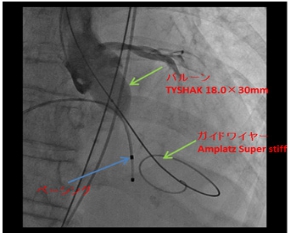

1.经皮冠状动脉腔内血管成形术(PTCA);经皮冠状动脉介入治疗(PCI),

2.冠动脉内支架留置(附图)

3.药剂涂膜气球(DCB )

5.慢性完全闭塞病变治疗(CTO)